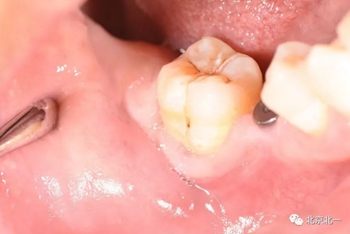

第一步:術(shù)中微創(chuàng)種植, 穿齦愈合。

直立后維持位置, 并取模戴牙。